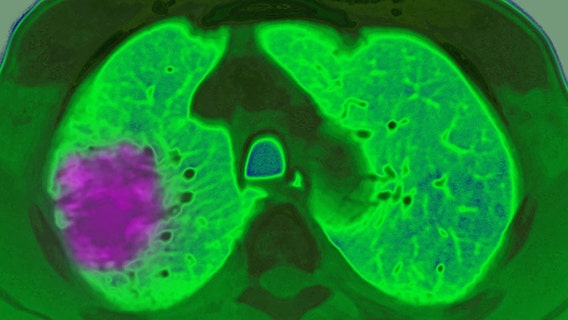

Lung cancer rising among non-smokers — here's why

The most common form of lung cancer is primarily found in non-smokers, a new study reveals. Doctors react to the surprising driver of the disease and other risk factors.